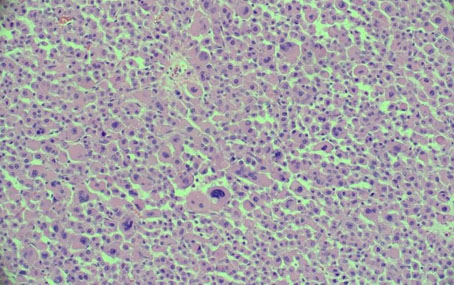

The histological characteristic of OAC is the presence of large polygonal cells with abundant eosinophilic cytoplasm, as a result of mitochondrial accumulation [3]. The diagnostic criteria used for ACC, the Weiss system, overestimates malignant potential in oncocytic tumors, therefore a separate classification system called the Lin–Weiss–Bisceglia (LWB) classification is used for oncocytic tumors [5],[8]. The LWB system divides oncocytic adrenocortical neoplasms (OANs) into benign, borderline, and malignant categories based on three main criteria: a mitotic rate greater than 5 per 50 high-power fields, vascular invasion, and metastasis. Malignancy is diagnosed if any of these criteria are present, while borderline tumors show only minor criteria, such as a tumor size greater than 10 cm, necrosis, or capsular invasion. This classification system has enhanced the ability to differentiate between benign oncocytic adenomas and OACs. In our patient, the resected specimen showed a well-circumscribed tumor weighing 5458 g, and measuring 26.0 × 25.0 × 16.0 cm. The tumor also had extensive hemorrhage and necrosis, along with a central fibrous scar [9]. Microscopically the patient’s tumor matched the classic histological findings for OAC and exhibited a low Ki-67 index of 2% suggesting a low proliferative rate. However, the tumor did exhibit vascular (renal vein) and capsular invasion (Figure 3, Figure 4, Figure 5, Figure 6). Based on the LWB criteria, malignancy was established due to the vascular invasion. Next-generation-sequencing (NGS) showed TP53 pathway alterations. The malignancy had a low tumor mutation burden and was found to be microsatellite stable. These findings are consistent with recent research suggesting a distinct mitochondrial metabolic profile with an oncocytic variant of ACC [4].

Figure 3: Sheets of tumor cells marked with atypia (H&E×20).